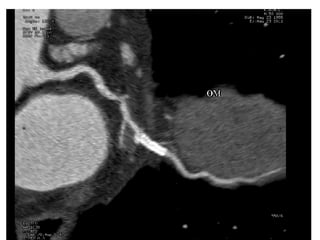

A 60-year-old male with multiple comorbid issues presented to the emergency room with chest pain. An ECG showed tall T waves and right bundle branch block. A CT/PET stress test revealed a small inferolateral infarct and significant peri-infarct ischemia. The patient was referred to cardiology to rule out acute coronary syndrome.